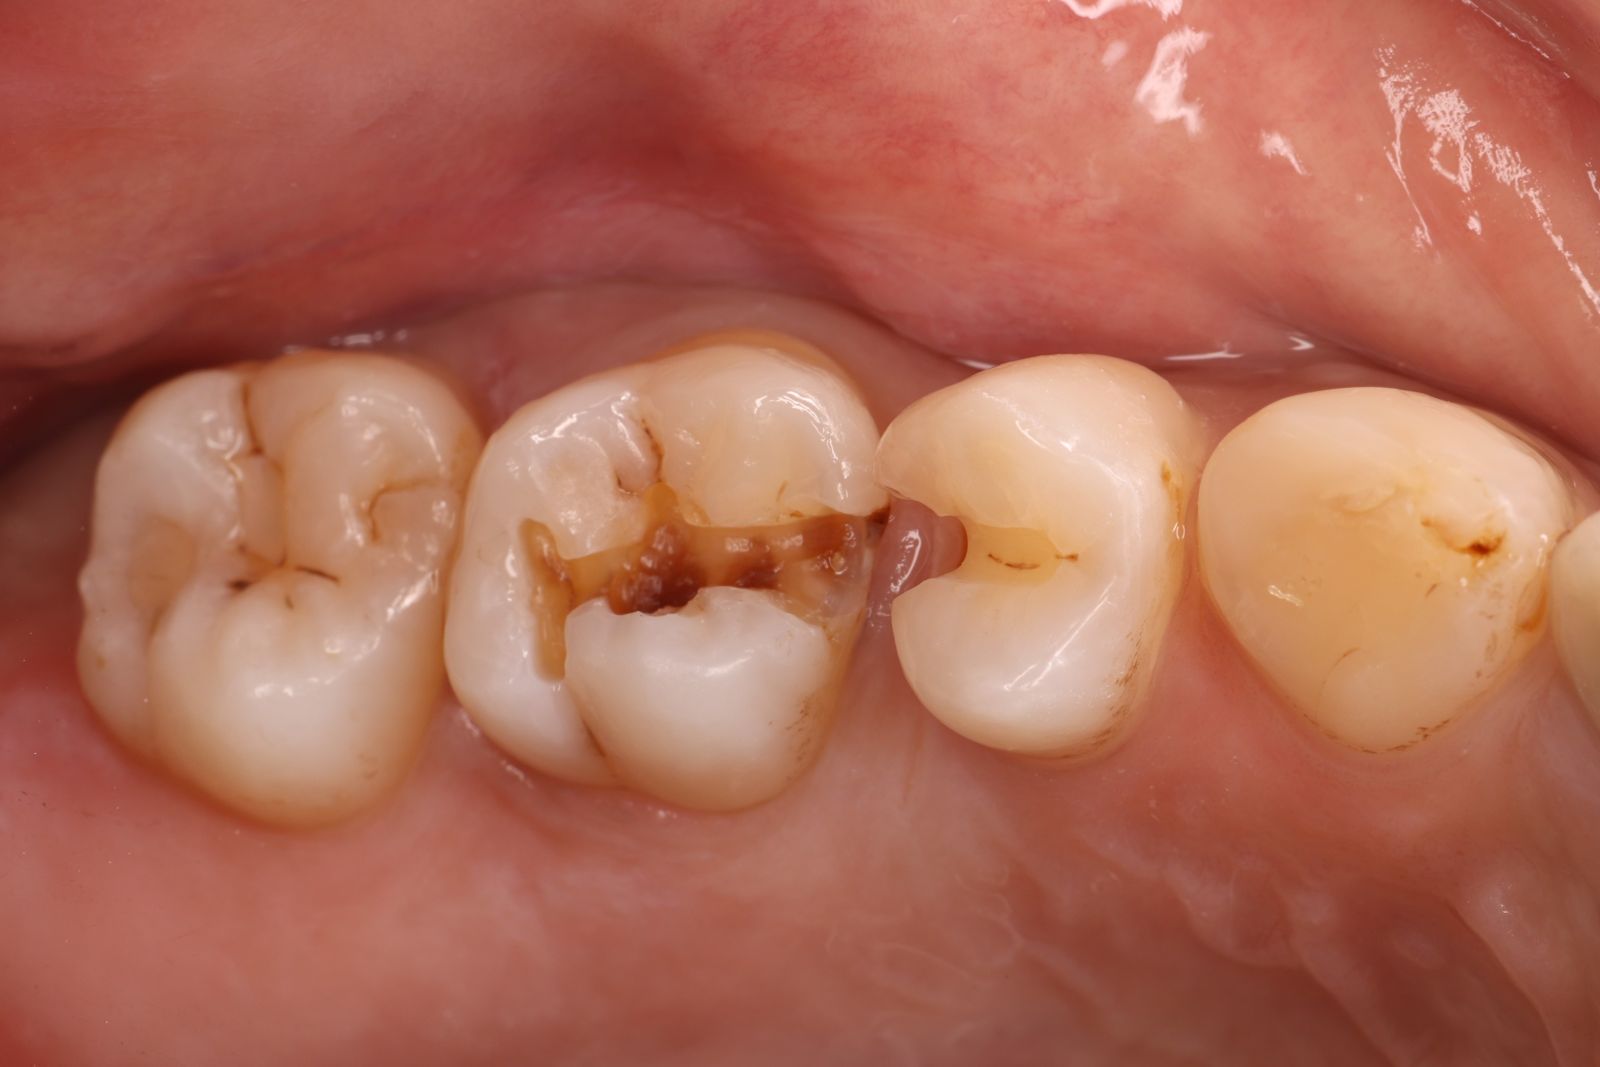

【 案 例 三】

- 有時候表面上看起來是蛀牙是一個小缺口,其實裡面已經是範圍很大的蛀牙了!用隔濕的小帳棚隔絕汙染、清理蛀牙,缺損的齒質就靠陶瓷齒雕(瓷塊)做修復!仿真的色澤及外觀,讓你看不出來牙齒曾經的損傷。